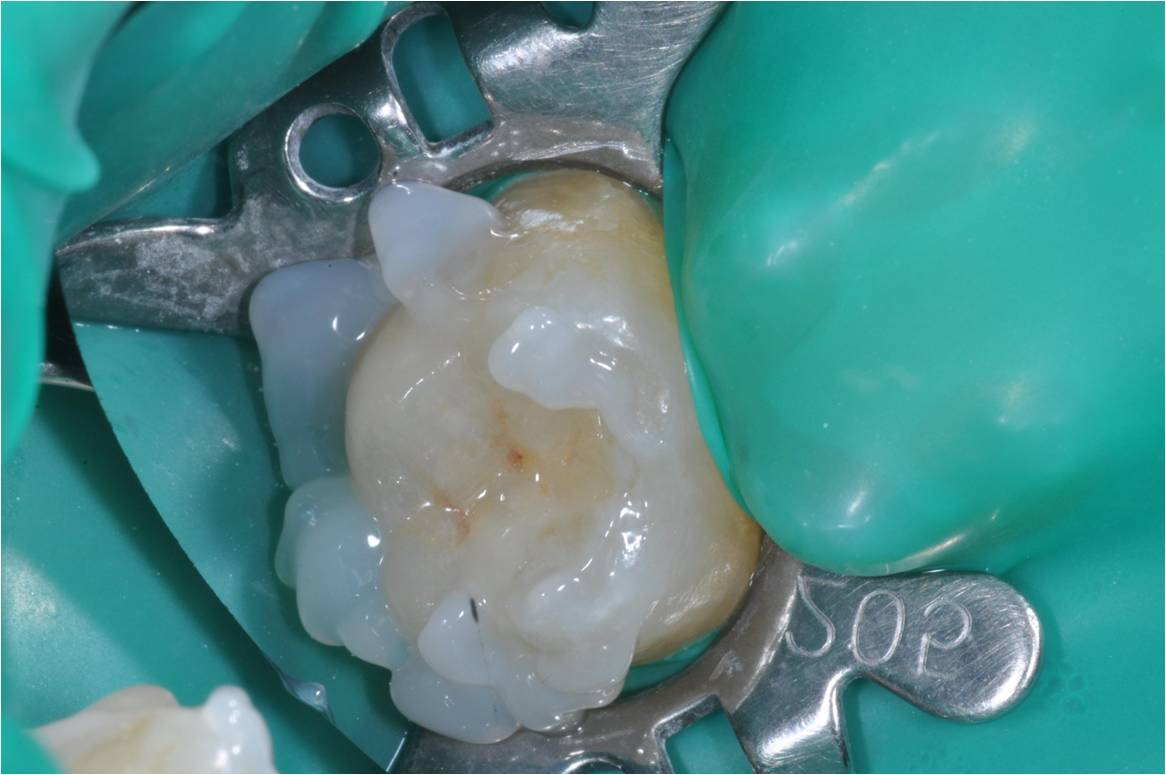

上椽皮障,以樹脂黏著劑,崁體黏著